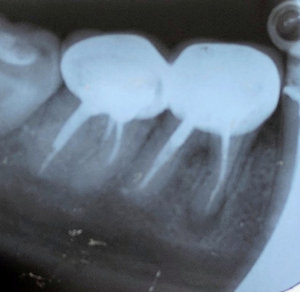

У меня сейчас стоят брекеты на нижней и верхней челюсти. Когда сделали общий снимок, у меня под коронкой на 6 зубе внизу слева оказалась киста. Врач предлагает сделать зубосохраняющую операцию с разрезанием десны и удалением кисты с корня зуба. Но меня одолевают сомнения.

Чтобы приступить к выполнению операции необходимо оценить размеры кисты зуба и её расположение. Для этих целей наиболее информативным методом диагностики является компьютерная томография.